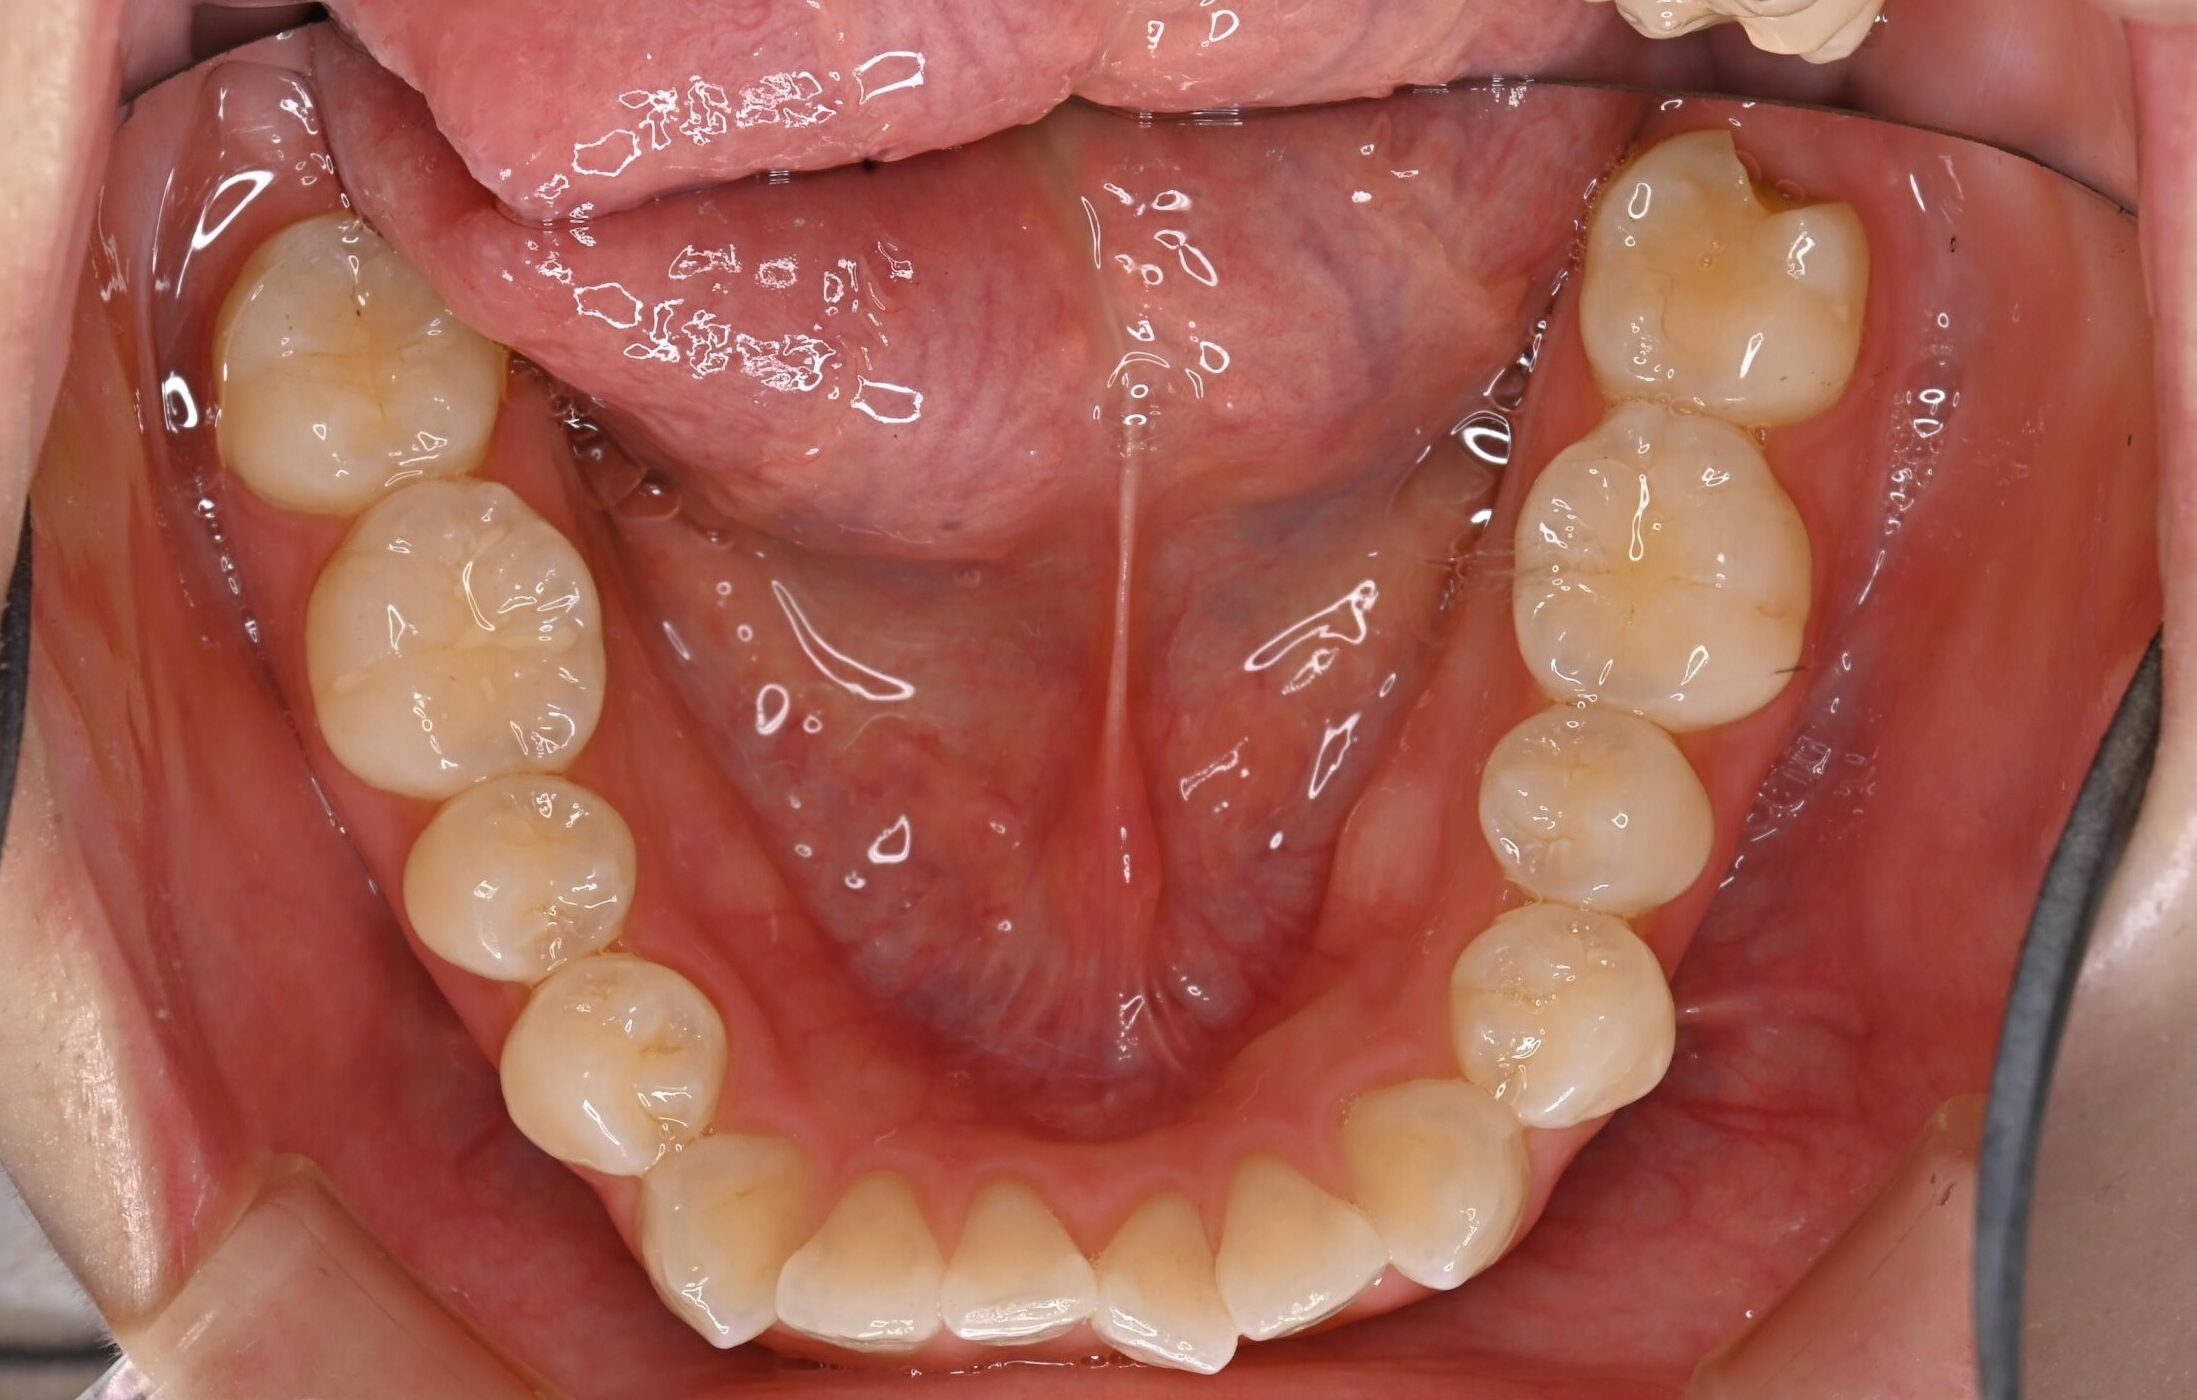

症例写真 before